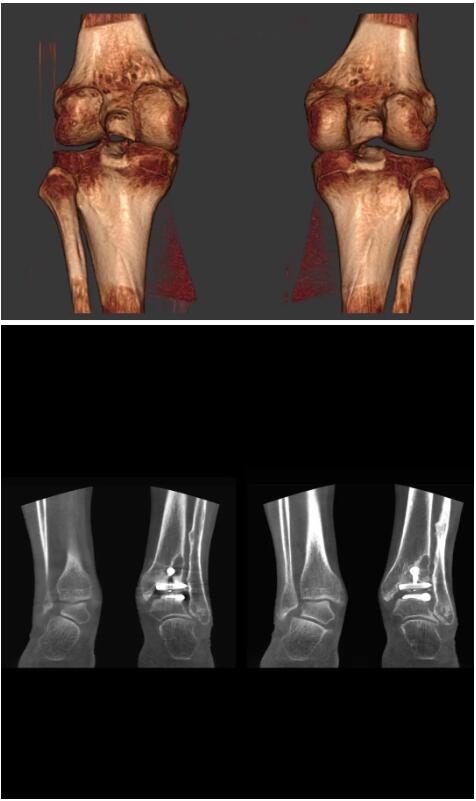

另外一款被稱為世界上最小的CT,它的重量僅300磅,不僅能夠掃查足部,還可以檢查膝蓋和上肢等。

與上面介紹的CT一樣,它同樣具有輻射低、占地空間小(23*36)的特點(diǎn),隨開隨用(支持直接接入墻上的插座)。

這款CT使用非常方便,通過上下移動保持與患者的手臂或者雙腿齊平,掃描快速,僅需要30秒左右就可以完成掃查。

以下是這些“特立獨(dú)行”的CT所拍出來的圖像: